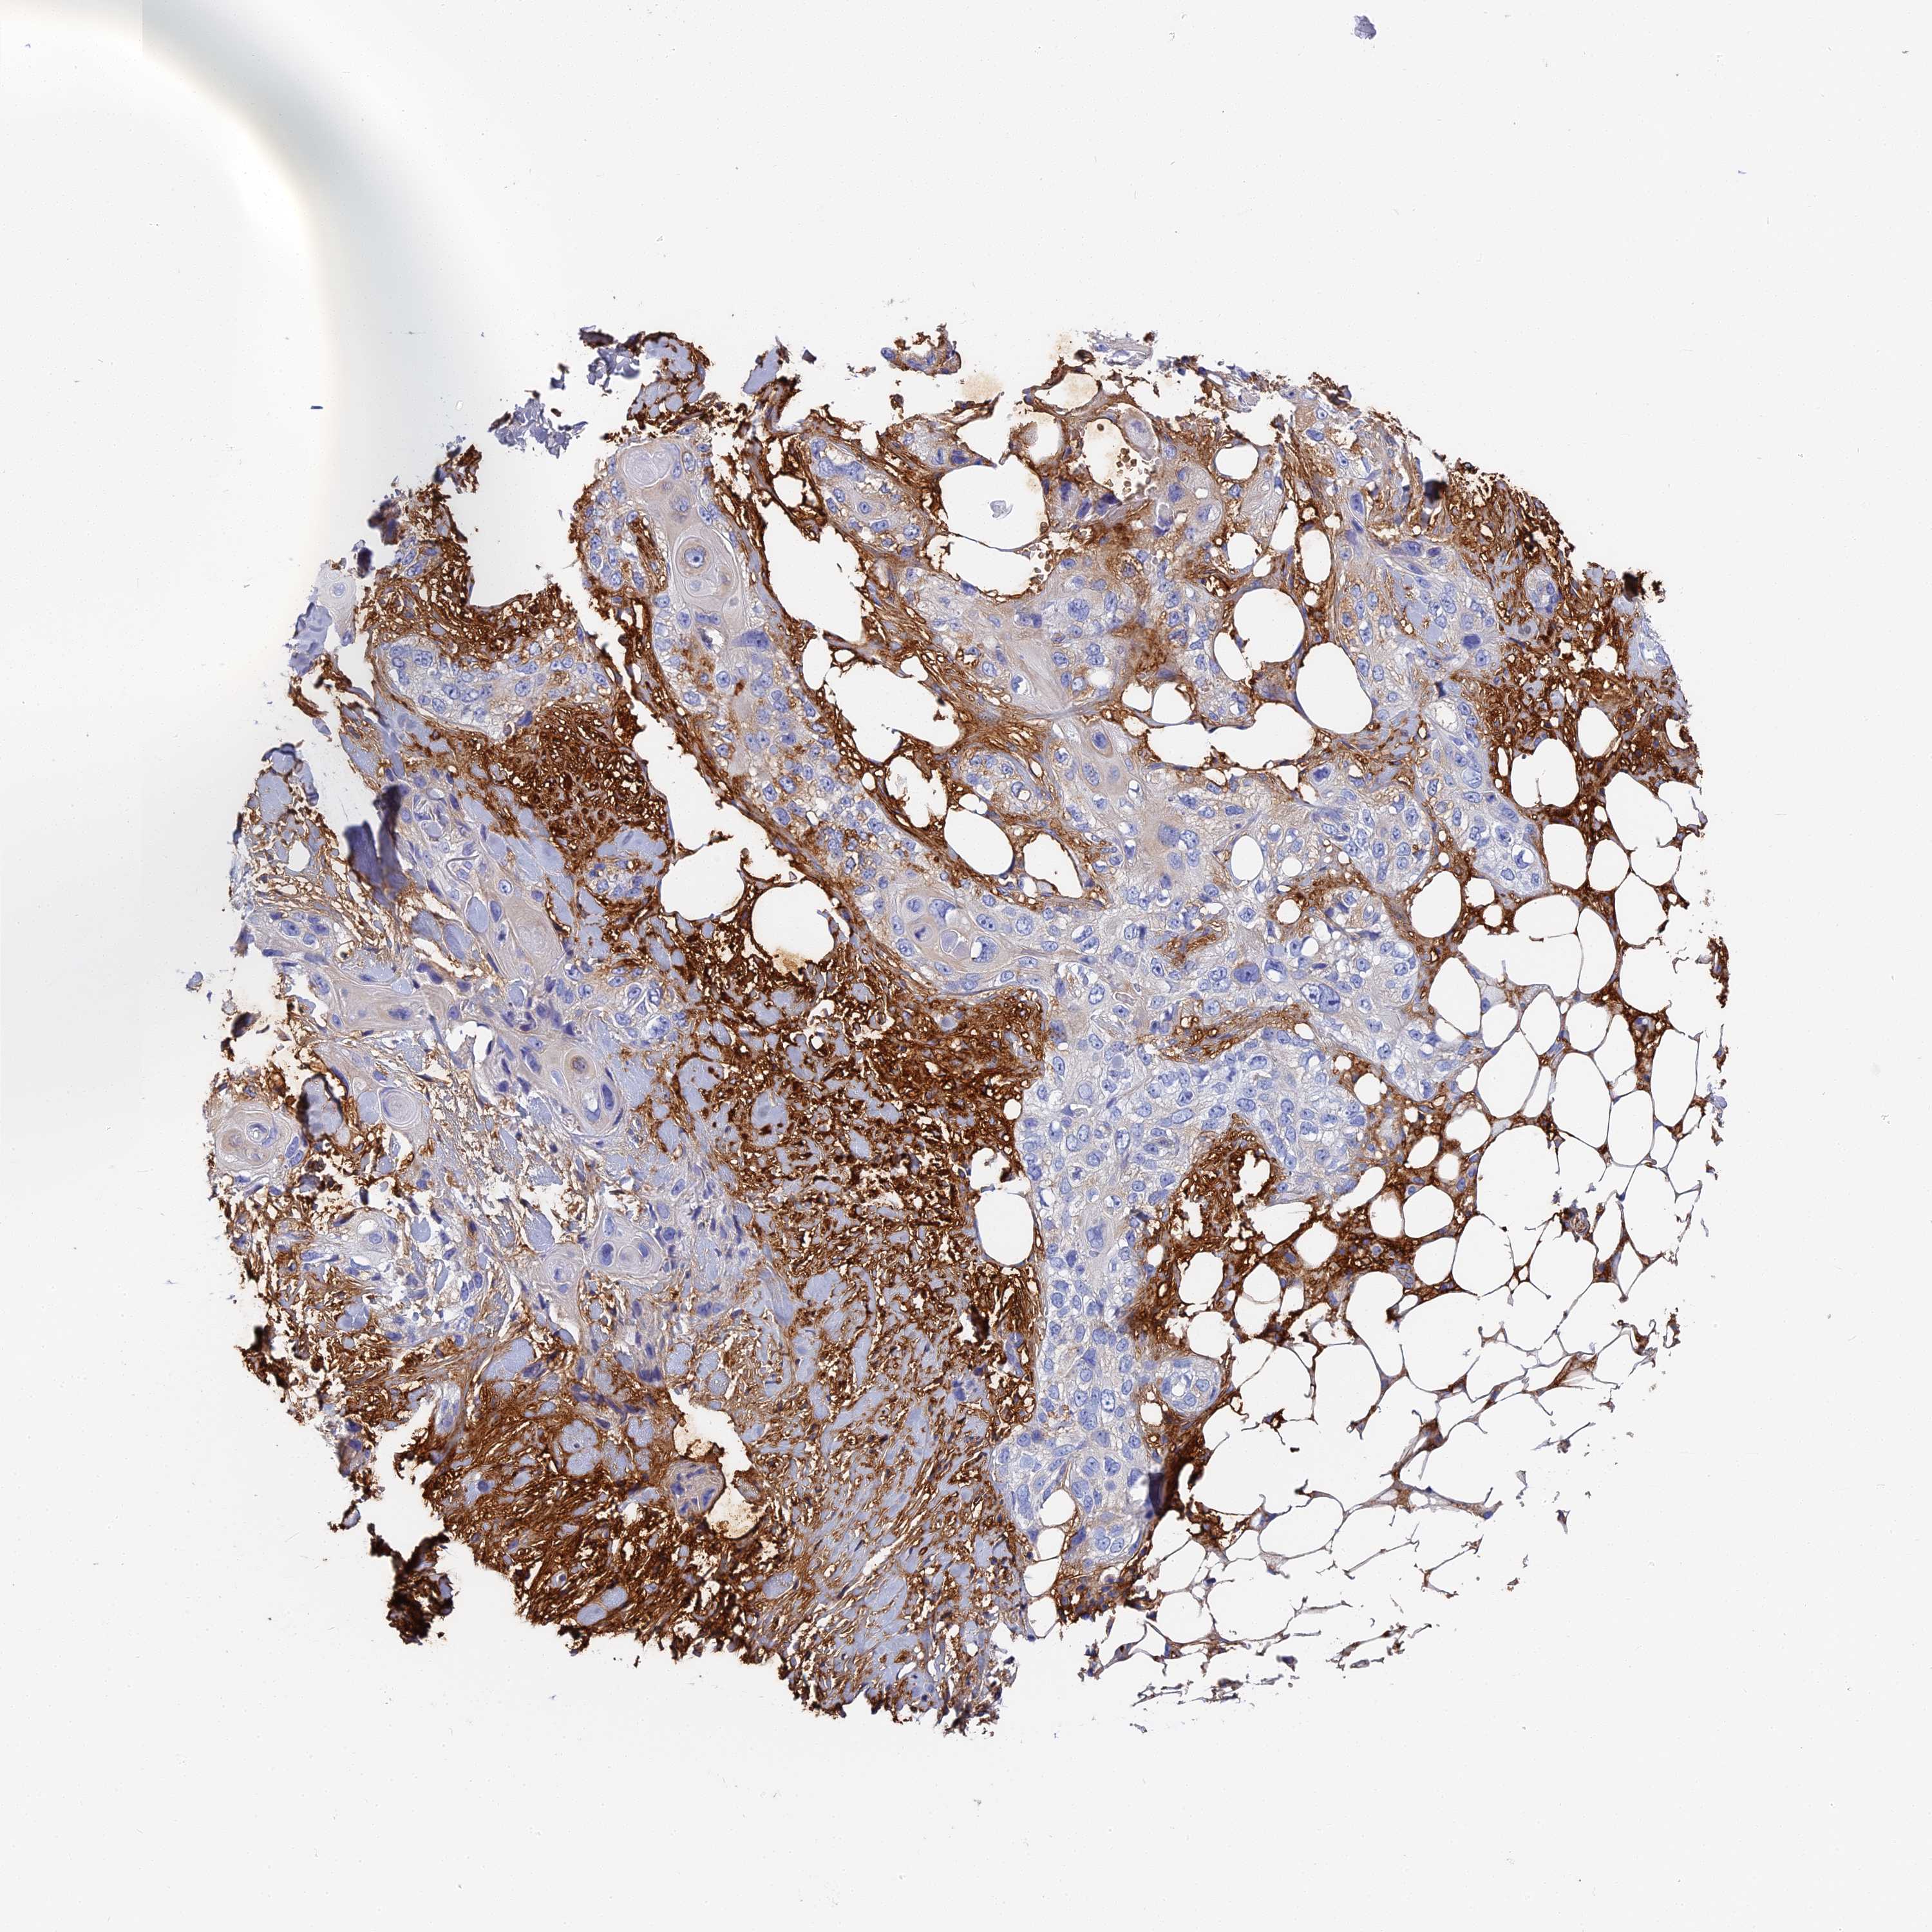

SKIN CANCER - Protein expressioni

A mouse-over function shows sample information and annotation data. Click on an image to view it in a full screen mode. Samples can be filtered based on level of antibody staining by selecting one or several of the following categories: high, medium, low and not detected. The assay and annotation is described here.

Antibody stainingi

Antibody staining in the annotated cell types in the current human tissue is reported as not detected, low, medium, or high, based on conventional immunohistochemistry profiling in selected tissues. This score is based on the combination of the staining intensity and fraction of stained cells.

Each image is clickable and will lead to virtual microscopy that enables deeper exploration of all samples and also displays staining intensity scores, fraction scores and subcellular localization as well as patient and tissue information for each sample.

Antibody HPA041639

Antibody HPA042049

Squamous cell carcinoma, metastatic, NOS

Squamous cell carcinoma, NOS